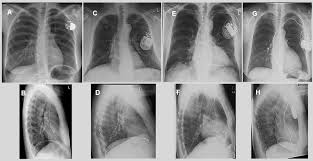

Icd Kardiowerter Defibrylator Fotos Facebook

Icd Kardiowerter Defibrylator Fotos Facebook from lookaside.fbsbx.com

Implantationen Umm Universitatsmedizin Mannheim

Implantationen Umm Universitatsmedizin Mannheim from www.umm.de